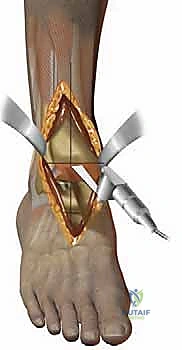

لفهم أهمية وتعقيد جراحة استبدال مفصل الكاحل، يجب أولاً أن نفهم كيف يعمل هذا المفصل الطبيعي المذهل. الكاحل ليس مجرد مفصل مفصلي بسيط (Hinge Joint) يتحرك لأعلى ولأسفل فقط، بل هو هيكل ديناميكي معقد يتحمل ضغوطاً هائلة تفوق وزن الجسم بعدة أضعاف أثناء المشي والجري.

يتكون مفصل الكاحل الأساسي (المفصل الظنبوبي الكاحلي - Tibiotalar joint) من التقاء ثلاث عظام رئيسية:

1. عظمة الظنبوب (Tibia): وهي عظمة الساق الكبرى، وتشكل السقف والجزء الداخلي من الكاحل (الكعب الداخلي - Medial Malleolus).

2. عظمة الشظية (Fibula): وهي عظمة الساق الصغرى، وتشكل الجزء الخارجي من الكاحل (الكعب الخارجي - Lateral Malleolus).

3. عظمة الكاحل (Talus): وهي العظمة السفلية التي تستقر داخل التجويف الذي تشكله عظمتا الساق، وتعمل كنقطة ارتكاز محورية للقدم.

تُغطى نهايات هذه العظام بطبقة ناعمة ومرنة تسمى "الغضروف المفصلي" (Articular Cartilage). هذا الغضروف يعمل كوسادة ممتصة للصدمات ويسمح للعظام بالانزلاق فوق بعضها البعض باحتكاك يكاد يكون معدوماً. علاوة على ذلك، يُفرز المفصل سائلاً زلالياً (Synovial Fluid) يعمل كزيت تشحيم لضمان نعومة الحركة. عندما يتضرر هذا الغضروف لأي سبب، تبدأ العظام بالاحتكاك المباشر، مما يسبب الألم الشديد، التورم، وفقدان القدرة على الحركة؛ وهنا تبرز الحاجة الماسة للتدخل الطبي.